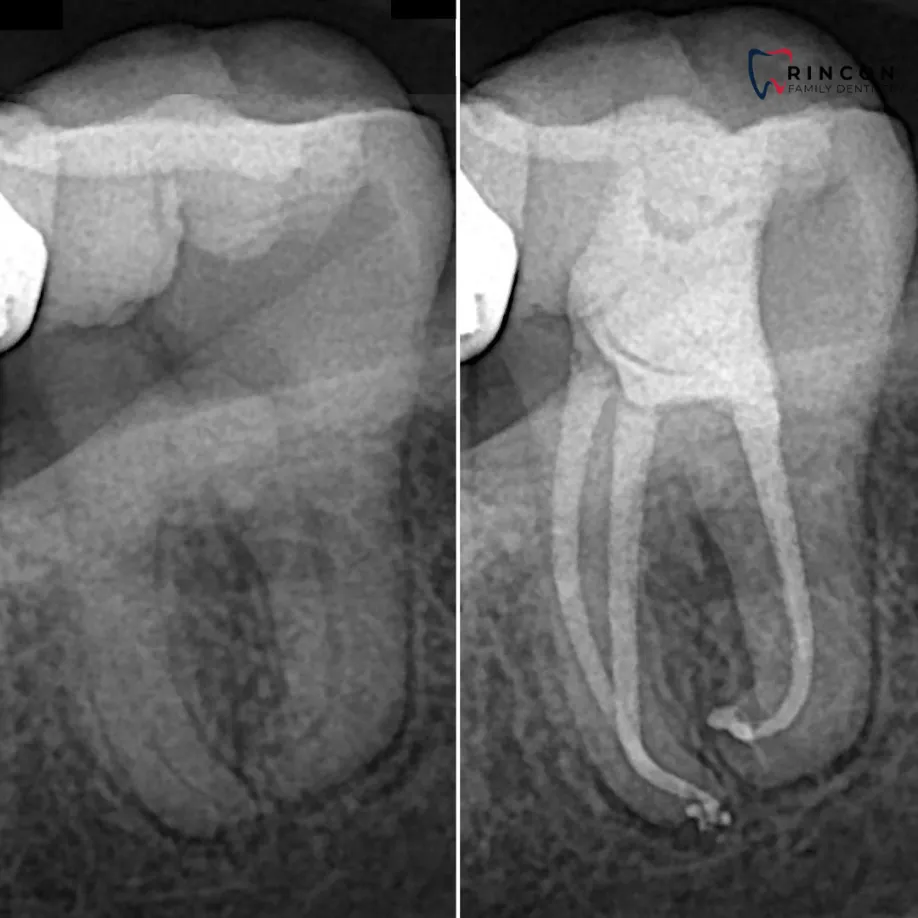

Periapical X-rays

If sharp pain or swelling appears near a specific tooth, a periapical scan helps identify decay, infection, or bone loss. It captures the full tooth from crown to root, offering a complete picture of its condition. Our advanced digital sensors deliver crisp results in seconds while keeping exposure low.

Dental Bone Loss X-ray

If your gums bleed often or your teeth feel loose, this X-ray checks the strength of the bone surrounding them. Our team uses detailed periapical imaging to assess bone density and catch thinning before it progresses.